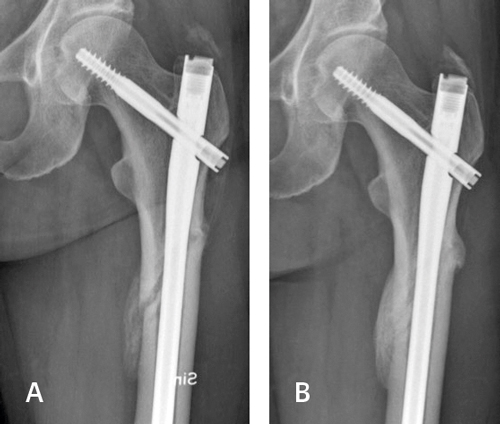

Kompletta atypiska femurfrakturer är bäst att märgspika med ett implant som samtidigt skyddar lårbenshalsen från framtida brott (Figur 3A och 3B). Läkningstiden är cirka 7 månader, och 10 procent av patienterna behöver revisionskirurgi för ofullständig läkning eller implantatkomplikationer [44].

Figur 3. Komplett atypisk femurfraktur en månad efter märgspikning (A) och efter fyra månader (B).